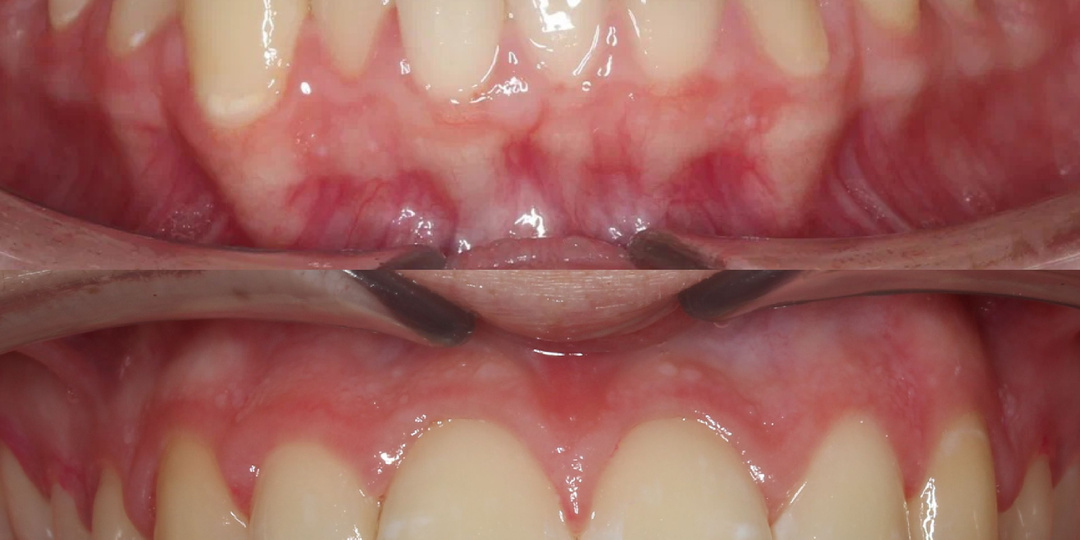

Клинический случай: дистопированные клыки и перекрёстный прикус 👇🏻 Сегодня расскажем о случае, где ортодонтическое лечение помогло не только выровнять зубы, но и полностью изменить эстетику улыбки После консультации врача-ортодонта было выявлены: • Перекрёстный прикус • Дистопированные клыки  (клыки, которые неправильно расположены в зубном ряду, например, повернуты вокруг оси или наклонены в сторону)  • Смещение средней линии • Суженный зубной ряд Мы провели лечение с помощью брекет-системы Damon Q и добились идеального результата 😍 Этот случай показывает, что даже сильно смещённые зубы можно вернуть в идеальное положение при грамотном ортодонтическом подходе. Брекеты — это не только про эстетику, но и про здоровье и функциональность прикуса! Дли записи на консультацию к врачу-ортодонту пишите в личные сообщения 💬 ⭐️ Рейтинг 5,0 на Яндекс.Картах  📍 Владимирский проспект, 7 📞 +7 921 399-41-17